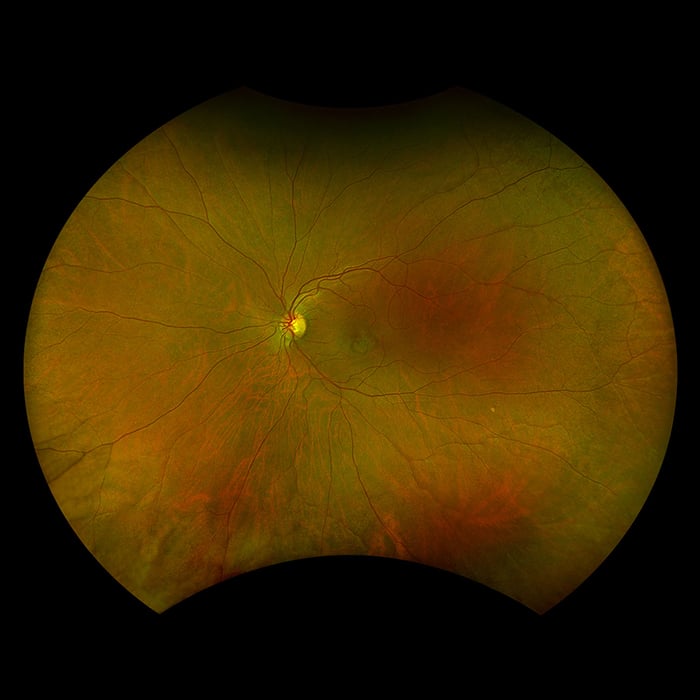

Silverstone RGB setzt neue Maßstäbe in der Netzhautbildgebung. Es ist das einzige Gerät, das in einer einzigen Aufnahme farbgetreue 200°-optomap-Ultraweitwinkelbilder erfasst - mit einem nahtlos integrierten, geführtem Swept-Source-OCT. Zum ersten Mal können Augenärzte in einem Gerät auf neun aussagekräftige Bildgebungsmodalitäten zugreifen, die jeweils für die Darstellung von Pathologien in der gesamten Netzhaut ausgelegt sind.

optomap verbessert nachweislich die Erkennung von Pathologien, das Management von Erkrankungen und Arbeitsabläufe in Praxen und Kliniken. Mit nun neun Modalitäten zur Netzhautbildgebung, darunter integriertes peripheres Swept-Source-OCT, erleichtert Silverstone RGB die Untersuchung der Netzhaut vom Glaskörper bis zur choroidal-skleralen Grenzfläche.

- Farbe rgb